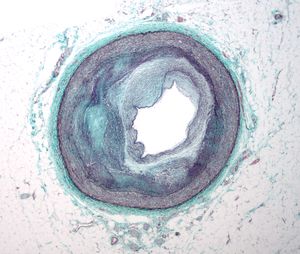

Micrograph of a coronary artery with the most common form of coronary artery disease (atherosclerosis) and marked luminal narrowing. Masson's trichrome.

إعاقة وصول الدم إلى القلب يسبب نقصا في تروية (موت الخلايا نتيجة نقص الأكسجين) الخلايا القلبية. عندما تموت الخلايا القلبية من نقص الأكسجين، تسمى هذه الحالة بالجلطة القلبية (تُعرف بالذبحة الصدرية). تؤدي الجلطة القلبية إلى تضرر عضلة القلب، موتها ولاحقا تكون ندبة في مكان الجلطة لا تستطيع الخلايا النمو فيها مجدداً. تحدث الجلطة القلبية غالباً نتيجة انسداد مفاجئ لشريان تاجي عند تمزق صفيحة عصيدية، والتي تسبب تنشيط جهاز التجلط الدموي، فينسد تجويف الشريان بالصفيحة الدهنية التي تفاعلت مع عناصر التجلط النشطة ليصل إلى مرحلة الانسداد الكامل المفاجئ. تمثل نسبة تضيق تجويف شريان القلب قبل الانسداد المفاجئ حوالي 20% من قطر التجويف، وذلك طبقا لدراسة إكلينيكية انتهت في أواخر التسعينات من القرن الماضي باستخدام جهاز الموجات فوق الصوتية لأوعية الدم Intravascular ultrasound خلال 6 أشهر قبل حدوث النوبة القلبية. وُجد أن انسداد تجويف الشريان بنسبة تزيد عن 75%، والتي تم رصدها باستخدام جهاز فحص الجهد القلبي Cardiac stress test، مسئول عن حالات النوبات القلبية بنسبة 14% فقط، بقية النسبة نتيجة تمزق الصفيحة الدهنية أو حدوث تقلص في الشريان في منطقة التصاق الصفيحة. الأسباب التي تؤدي إلى تمزق الصفيحة الدهنية تبقى غير مفهومة تماماً. أيضا يتسبب في حدوث الجلطة القلبية، ولكن بنسبة اقل، تقلص جدار الشريان، وهي حالة تصاحب الصفيحات الدهنية وأمراض الشرايين التاجية. يرتبط حدوث أمراض الشرايين التاجية مع التدخين، السمنة، ارتفاع ضغط الدم، والنقص المزمن في فيتامين سي. يعتبر وجود تاريخ عائلي بالإصابة بأمراض الشرايين التاجية مؤشر قوي لاحتمال الإصابة بالمرض. يتضمن المسح عن أمراض الشرايين التاجية معرفة مستوى الهيموسِستين homocysteine، مستوى البروتينات الدهنية عالية الكثافة HDL، مستوى البروتينات الدهنية منخفضة الكثافة LDL ومستوى الدهون الثلاثية Triglyceride.